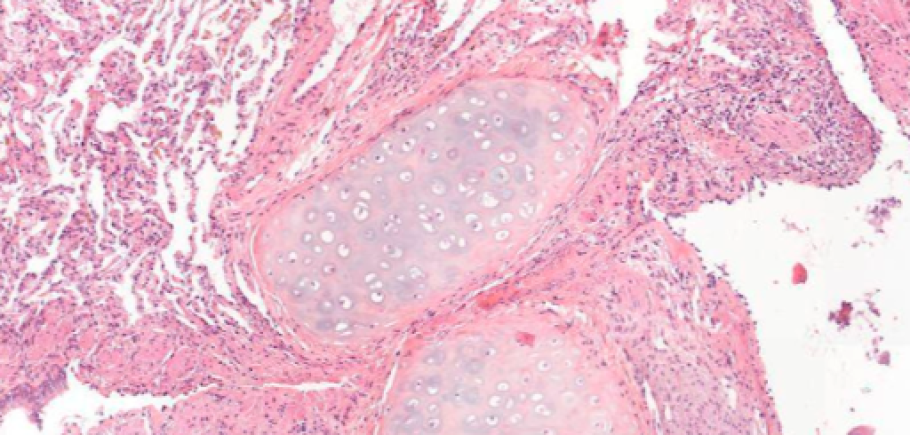

Pour ce Data Challenge, les compétiteurs devront développer un algorithme d’intelligence artificielle (IA) permettant de prédire si le patient présente des signes de rejet de greffe pulmonaire. Pour ce faire, les compétiteurs analyseront les données issues de lames d’anatomopathologie numérisées de biopsies de greffons. Cet examen consiste à étudier des tissus prélevés sur un patient pour repérer et analyser des anomalies liées au rejet de greffe. Le but ici sera d’identifier sur le tissu pulmonaire les zones pathologiques. L’objectif de ce challenge est d’aider au diagnostic du rejet de greffe en améliorant la reproductibilité dans l’identification des zones pathologiques.

Dans les phases de préparation du Data Challenge, un important travail d’annotation des données a été effectué par des experts internationaux. Lors de cette étape, les médecins pathologistes ont identifié les zones d’intérêt sur les lames numérisées. C’est à partir de ces annotations que les compétiteurs pourront entraîner leurs algorithmes pour tenter de reproduire de façon automatique le travail des experts sur de nouveaux échantillons.